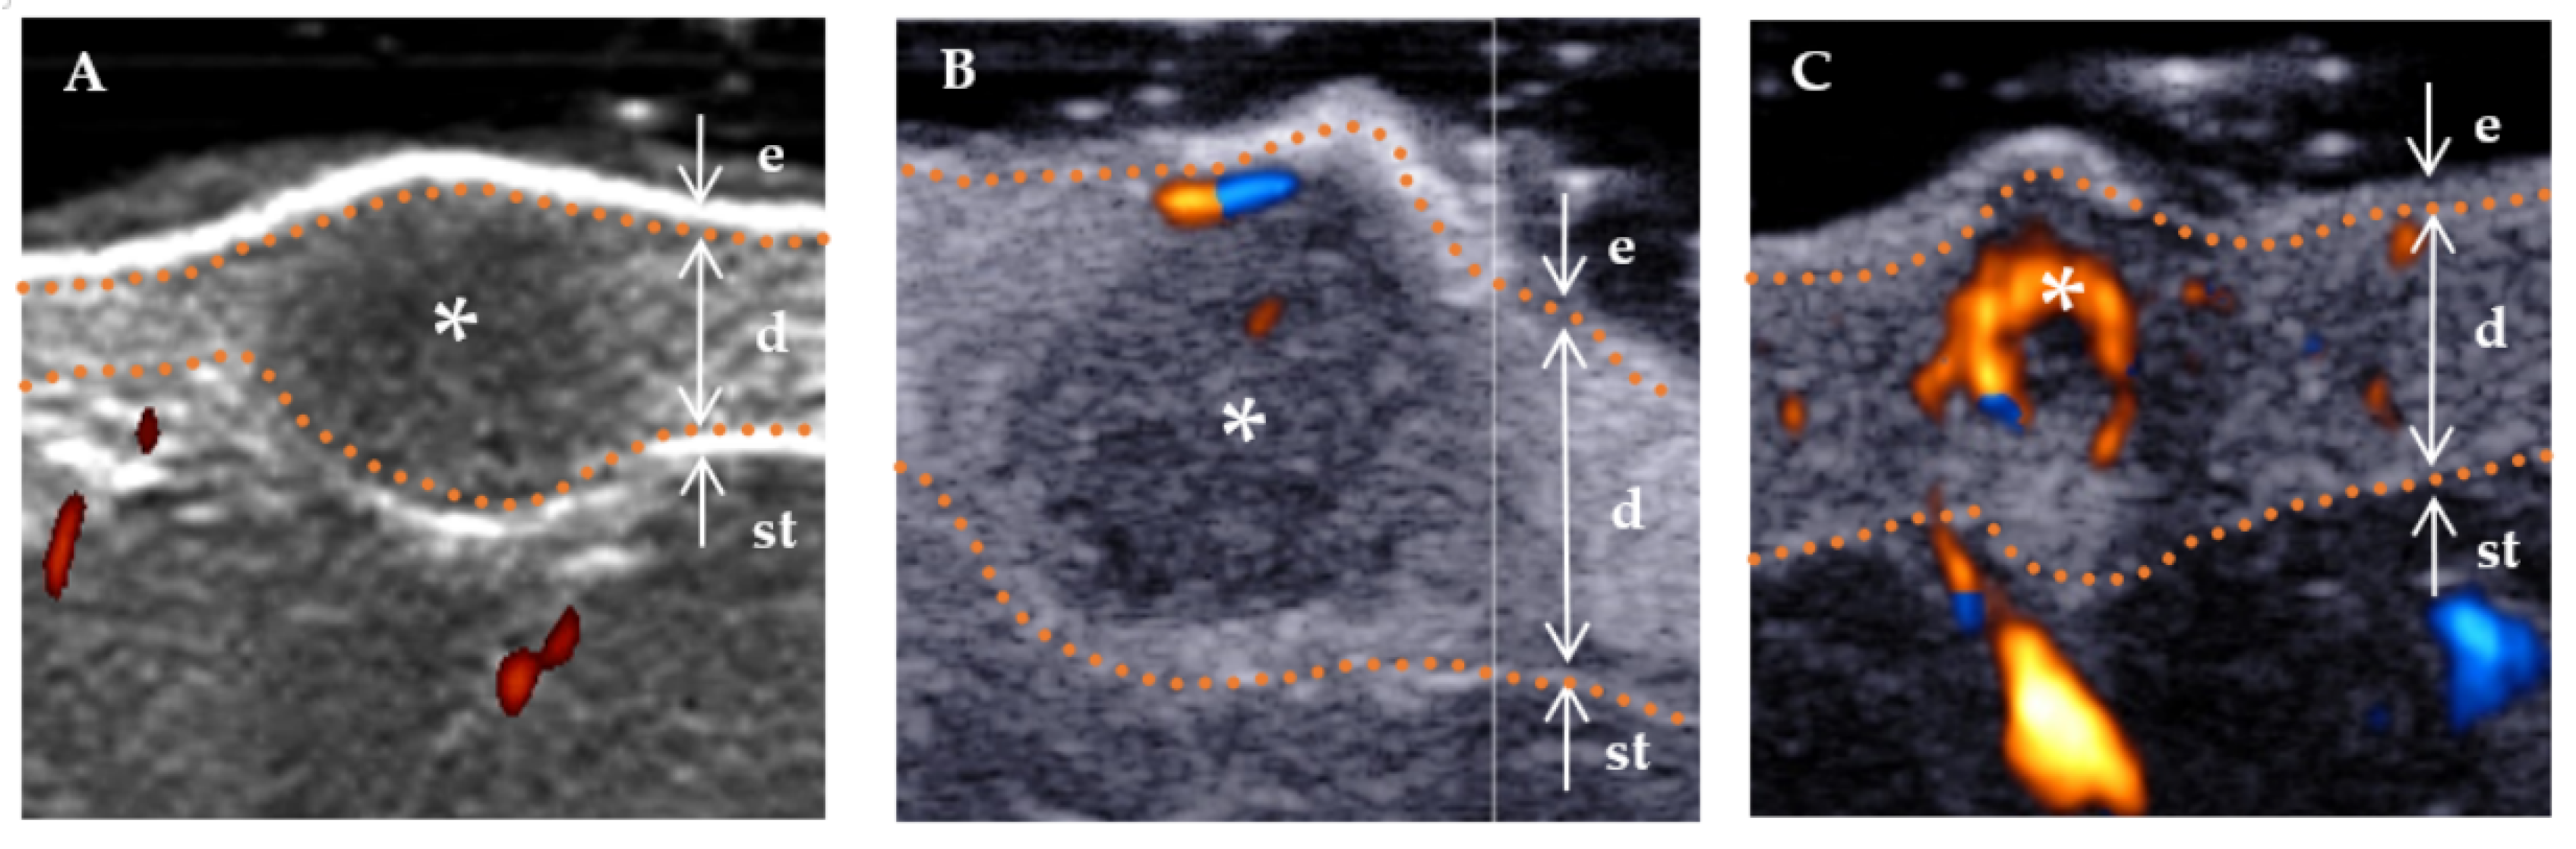

Figure 4.

Color Doppler flow grading using high-frequency ultrasound. The color red is used to indicate the direction of blood flow towards the transducer, while blue is used to indicate the direction of blood flow away from the transducer. * Indicates the precise location of the lesion on the ultrasound image. The skin layers are indicated by dotted orange lines, with arrows indicating a hyperechoic epidermis (e), an isoechoic dermis (d), and a subcutaneous tissue (st). (A) No blood flow signal (absent), that is, no blood flow inside the lesion. (B) Rare blood flow signals (sparsity), that is, a less than two punctate and/or short rod-like blood flow, and the rod blood flow did not exceed the radius of the lesion. (C) Rich blood flow signals (profusion), that is, more than three punctate vessels or long vessels, could be seen penetrating the lesion, and the length could be close to or beyond the radius of the lesion.